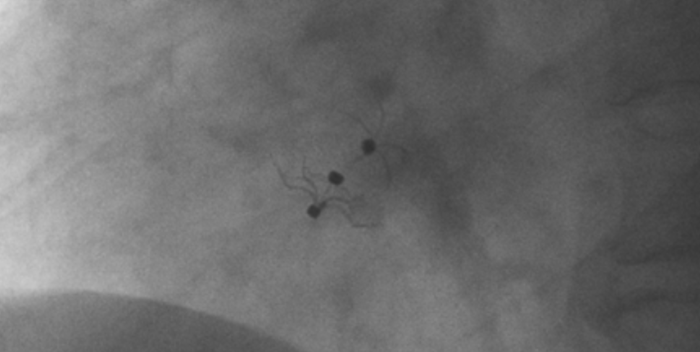

影像顯示試驗器械適應(yīng)性貼合于房間隔兩側(cè)且穩(wěn)定

術(shù)中造影顯示患者為PFO且長隧道型,目前市場上已商業(yè)化的PFO封堵器難以滿足該患者解剖結(jié)構(gòu)封堵需求。迪創(chuàng)醫(yī)療自主研發(fā)的OmniSeal PFO封堵器自適應(yīng)性雙盤貼合設(shè)計能廣泛適應(yīng)不同PFO隧道長度的解剖結(jié)構(gòu)和形態(tài),其雙盤外包覆式阻流和隧道內(nèi)填充阻流相結(jié)合的雙重阻流設(shè)計,可為此患者實現(xiàn)有效封堵。與此同時,OmniSeal首創(chuàng)的完全可穿刺式設(shè)計,也為此患者最大程度地保留了房間隔區(qū)域穿刺通道,以實現(xiàn)全兼容未來可能的左心系統(tǒng)二次介入術(shù)。術(shù)終造影和心臟超聲顯示封堵完全、效果良好。作為OmniSeal的首例臨床應(yīng)用,本次手術(shù)的順利完成和優(yōu)異效果充分體現(xiàn)了產(chǎn)品的設(shè)計創(chuàng)新優(yōu)勢。

迪創(chuàng)醫(yī)療自主研發(fā)的OmniSeal PFO封堵器系統(tǒng)具有多項創(chuàng)新設(shè)計和技術(shù)優(yōu)勢,并且對于目前市場商業(yè)化產(chǎn)品的多個臨床痛點(diǎn)問題,如難以開展左心系統(tǒng)二次微創(chuàng)介入手術(shù)、術(shù)后新發(fā)心房顫動、殘余分流、血栓形成等器械相關(guān)的限制和并發(fā)癥等,提供了針對性的解決方案。OmniSeal PFO封堵器系統(tǒng)獨(dú)創(chuàng)的完全可穿刺式設(shè)計,能實現(xiàn)全兼容左心系統(tǒng)二次介入術(shù)。其較高的適應(yīng)性使得產(chǎn)品可以適應(yīng)不同卵圓孔未閉解剖學(xué)結(jié)構(gòu)和形態(tài),并減少對房間隔的刺激, 降低術(shù)后心律失常事件。同時,雙盤外包覆式阻流和隧道內(nèi)填充阻流相結(jié)合的創(chuàng)新結(jié)構(gòu)在確保有效封堵的情況下,減少殘余分流,降低血栓形成。